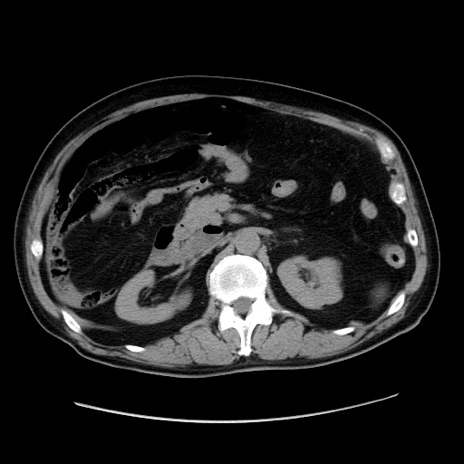

症例30(横断像)

【症例】80歳代男性

【主訴】臍周囲痛

【現病歴】約6時間前から臍下部痛が出現。次第に腹部膨隆・背部痛も生じてきたため来院。背部痛の場所は変化しない。

【身体所見】意識清明、BT 36.3℃、BP  131/87mmHg、P 87bpm、SpO2 100%(RA)、臍周囲自発痛・圧痛あり、反跳痛なし、自発痛部位に一致して板状硬あり、腹部膨隆、腸雑音減弱、CVA tenderness両側陰性。

【データ】WBC 19600、CRP 0.33